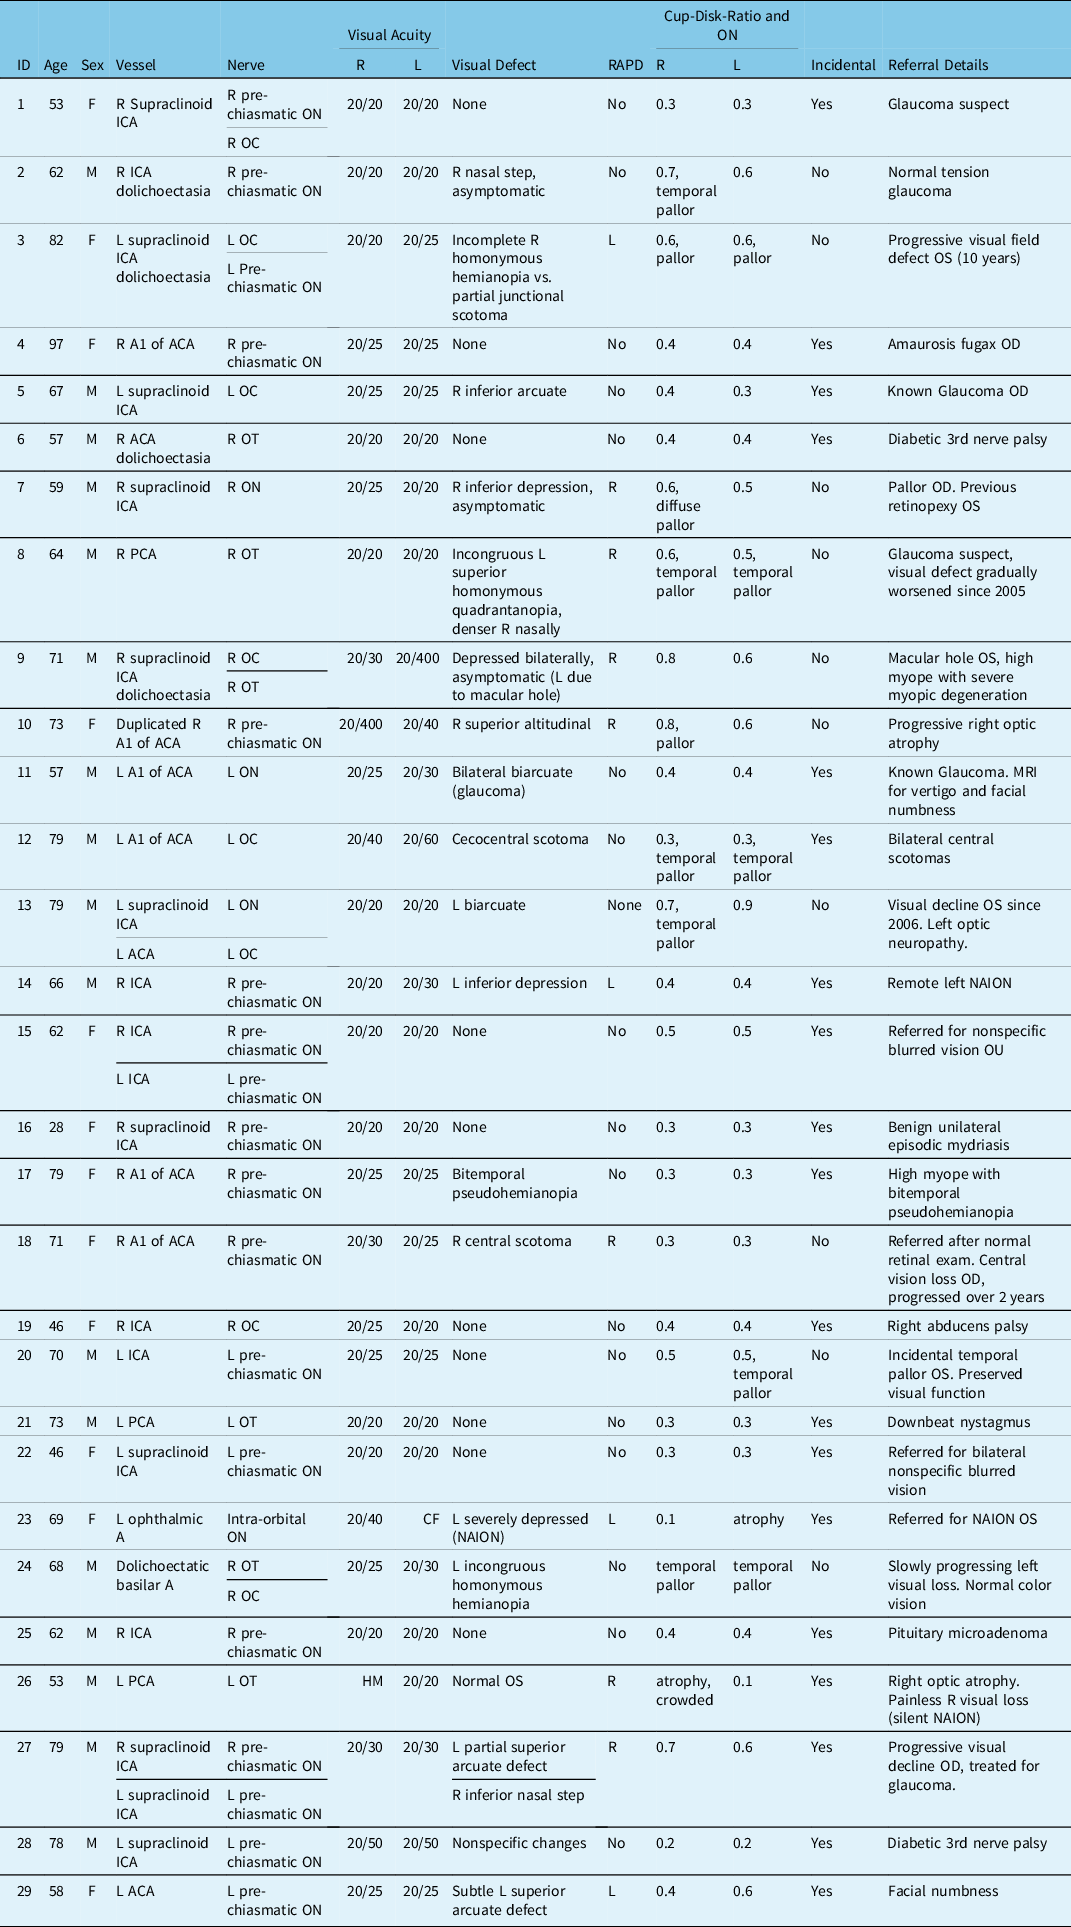

Table 1: Summary of patient demographics and clinical information

A = Artery; ACA = Anterior cerebral artery; CDR = Cup-to-disk ratio; HVF = Humphrey visual field; ICA = Internal cerebral artery; L = Left; LCA = Long circumferential artery; N = Nerve; NAION = Non-arteritic anterior ischemic optic neuropathy; NVC = Neurovascular conflict; OC = Optic chiasm; OD = Right eye; ON = Optic nerve; OS = Left eye; OT = Optic tract; PCA = Posterior cerebral artery; R = Right; RAPD = Relative afferent pupillary defect; VA = Visual acuity.

The most common NVCS (5/36, 13.8%) included the pre-chiasmatic optic nerve and supraclinoid internal cerebral artery. NVCS was an incidental finding in 19 patients (65.5%). These patients were imaged for other purposes such as oculomotor nerve palsy, nonarteritic anterior ischemic optic neuropathy, and downbeat nystagmus. They had no RAPD, optic disk changes, or visual defects secondary to the NVCS. 10/29 cases (34.5%) presented with visual field defects in variable patterns which localized to the NVCS site (cases 2, 3, 7–10, 13, 18, 20, and 24). OCTs were collected when available (72.4%, 21/29) (Table 2). When OCTs were obtained, RNFL atrophy was evident in many symptomatic cases of NVCS. Visual defects varied based on the site of the compression, which included retinal nerve fiber layer defects (such as nasal step, arcuate defects, and central scotomas), diffuse loss, incongruous homonymous hemianopia, and homonymous quadrantanopia. Eleven (37.9%) patients had normal visual fields. 31.0% (9/29) of patients (cases 1–3, 5, 8, 10, 11, 13, and 27) were referred to rule out non-glaucomatous pathology by glaucoma specialists. 55.5% (5/9) of these (cases 2, 3, 8, 10, and 13) patients were found to have visual field defects matching the NVCS, rather than normal tension glaucoma (NTG).

Table 2: Summary of most recent available OCT results

GCC = Ganglion cell complex; L = Left; R = Right; RNFL = Retinal nerve fiber layer.